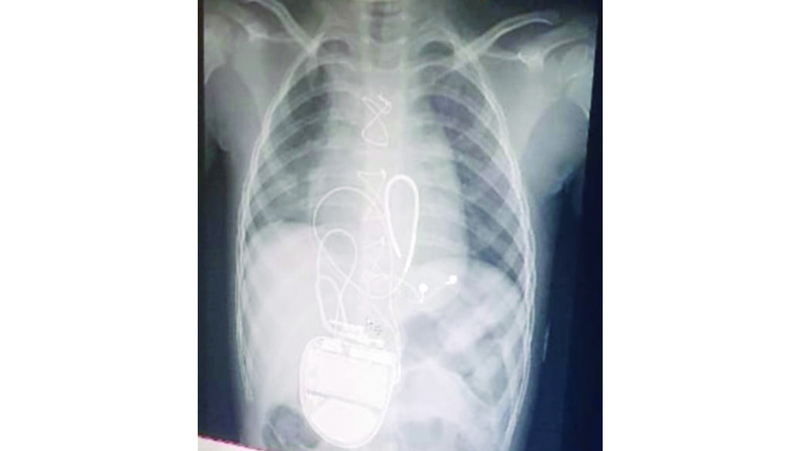

وقد خضعت (مريم) لعملية جراحية في مستشفى الجليلة التخصصي للأطفال، لتركيب جهاز مقوم نظم القلب ومزيل الرجفان القابل للزراعة، ووفقاً لتقرير طبي، فهي تحتاج إلى علاج طبيعي مكثف ووظيفي لمدة عام كامل تبلغ كلفته 372 ألف درهم، لكن ظروف أسرتها المالية المتواضعة منعتها من استكمال هذا الجزء من العلاج، ما حدا بأسرتها إلى مناشدة أهل الخير وذوي القلوب الطيبة مساعدتها على سداد كلفة علاج طفلتها، حتى تتمكن من استعادة قدرتها على الحركة والكلام.

وأوضح (أبومريم) أنه تم تشخيصها من الأطباء بأنها تعاني وجود أضرار بسبع مناطق في الدماغ، لا يصل إليها الدم، ما تسبب في فقدانها القدرة على الكلام، وإصابتها بشلل رباعي أفقدها القدرة على الجلوس والتحرك والأكل إلا عن طريق أنبوب التغذية، وقال: «أكّد الأطباء أنها تعاني مرض الورم العضلي المخطط، ما يُسمى بـ(ربدومايلوما)، وأنها تحتاج إلى عملية جراحية في القلب، لتركيب جهاز يُسمى مقوم نظم القلب ومزيل الرجفان القابل للزراعة، لمنع إصابتها بالسكتات القلبية المفاجئة، فنقلتها إلى مستشفى الجليلة التخصصي للأطفال، وخضعت لعملية جراحية».